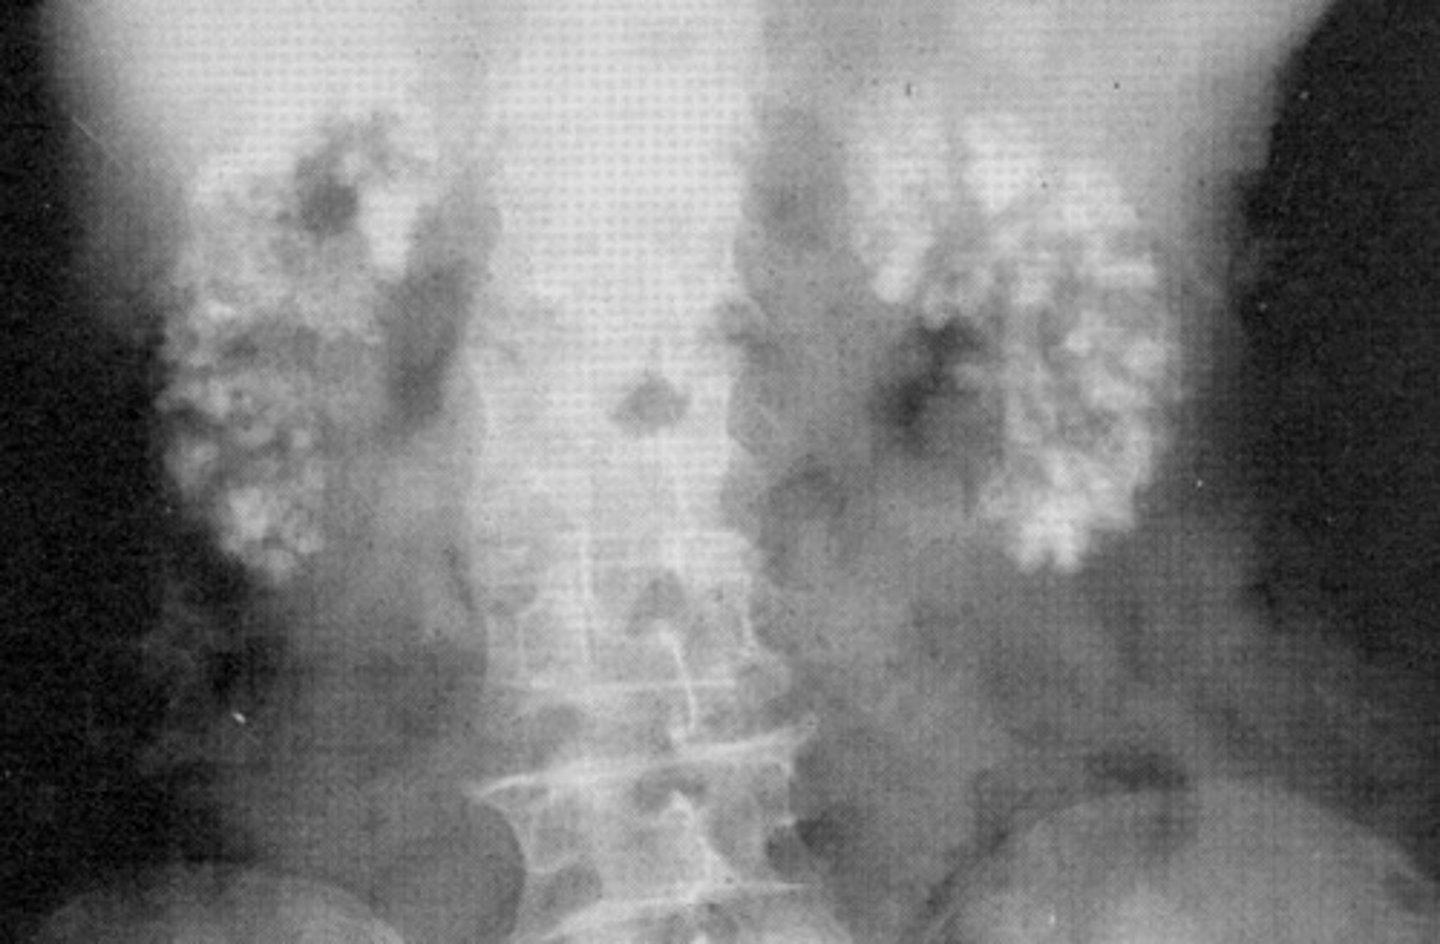

- Nephrocalcinosis

- Hypervitaminosis and Hyperthyroidism

- What refers to calcium deposits in the renal parenchyma that is caused by disorders that affect the calcium levels in the body?

- What are the disorders that cause this pathology?